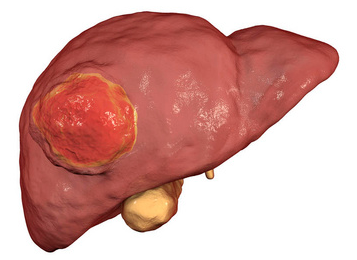

肝細胞癌簡介:

肝細胞癌,是指肝細胞發生的惡性腫瘤。原發性肝癌是全球常見惡性腫瘤之一,是目前我國第4位常見惡性腫瘤及第2位腫瘤致死病因,主要包括肝細胞癌(Hepatocellular carcinoma,HCC)、肝內膽管癌(Intrahepatic cholangiocarcinoma,ICC)和混合型肝細胞癌-膽管癌(Combined hepatocellular-cholangiocarcinoma,cHCC-CCA)三種不同病理學類型,三者在發病機制、生物學行為、病理組織學、治療方法以及預后等方面差異較大,其中HCC占75%~85%、ICC占10%~15%。